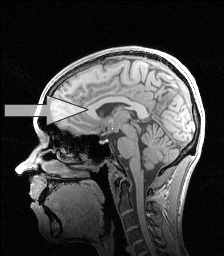

The corpus callosum is the main transverse tract of fibers that connects the two cerebral hemispheres. It is made of more than 200 million nerve fibers. The primary function of the corpus callosum is to integrate motor, sensory, and cognitive activity between the left and right hemispheres. A cross-section of the corpus callosum looks somewhat like a ball-peen hammer.

An MRI of a normal brain.

The arrow points to the corpus callosum.

The anterior portion of the corpus callosum is the genu, which curves ventrally and forms the rostrum. Continuing posteriorly the callosum becomes the body and then ends with the enlarged splenium. The corpus callosum develops during the 12 – 16th week of fetal gestation. Once formed, the callosum thickens with increasing myelination, except during a period of axonal elimination near birth. Postnatally the corpus callosum undergoes a burst of growth during the first four years of life.